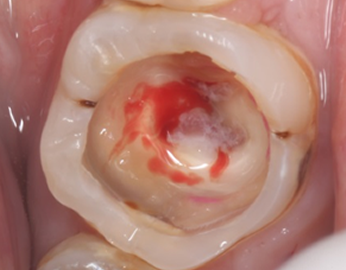

①抜髄治療

(イニシャルトリートメント)

虫歯が重度に進行すると、歯の内部にある神経に虫歯菌による感染症状が起きます。

これを解消するためには、神経を除去する必要が生じます。これを抜髄治療と呼びます。

抜髄においては、過不足なく神経を除去・消毒することが求められます。

マイクロスコープによって精密に取り残しなく処置を進めることで、歯の延命に繋がります。